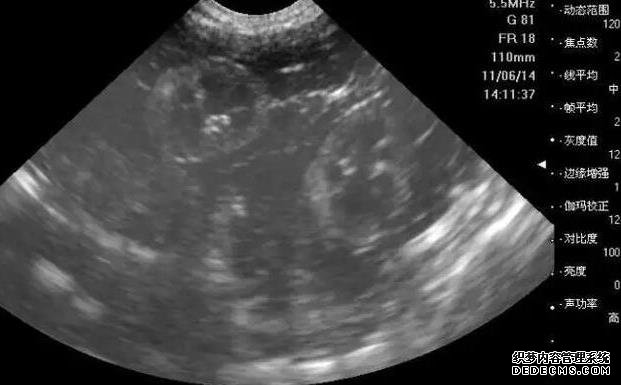

3、腹部彩超检查:通过B超确定子宫内部环境是否正常,如大小形态如何、是否存在宫腔疾病,子宫内膜是否适合着床等。